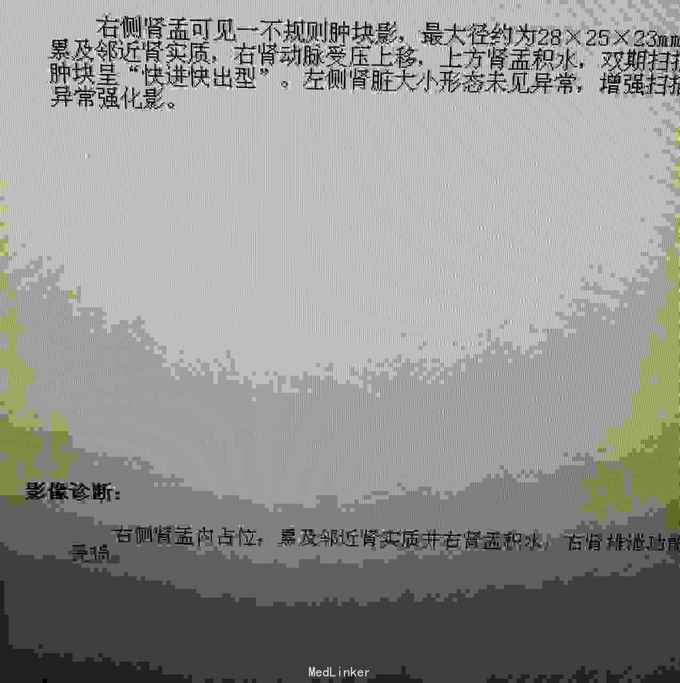

超声示:右肾积水,右肾盂内可见异常回声,不除外新生物,前列腺增生。CT示:右肾门占位,累及邻近肾实质并右肾积水,右肾排泄功能受损,考虑右肾肾盂肿瘤性病变。初步诊断为:1.右肾盂肿瘤(TI1N0M0)2.右肾积水 3.前列腺增生。

病理诊断为:右肾盂隆起型高级别乳头状尿路上皮癌,未侵及被膜。